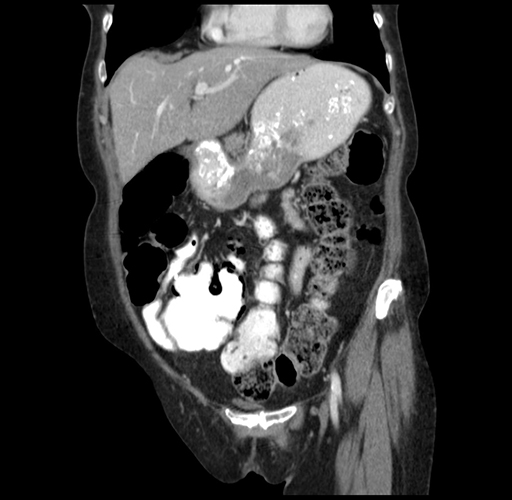

Pre-Chemo: Coronal Venous

Coronal Venous